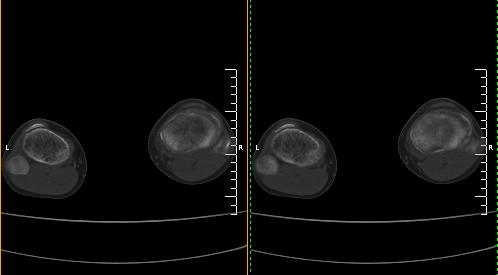

标题: CT19091:右胫骨近段骨性突出.

男,15岁,右胫骨近段软组织肿胀,下肢疼痛10左右.

右胫骨近端内侧骨性突起,皮质连续,骨质结构正常,首先考虑胫骨骨软骨瘤,随访观察。

右胫骨骨软骨瘤可能性大。